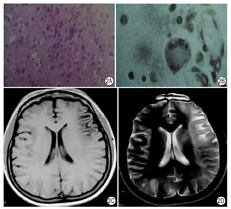

病理改变:PML病理表现为少突神经细胞受到乳多空病毒的选择性破坏,引起脱髓鞘。脑白质内有多灶性损害,形成脱髓鞘融合区,大脑半球比小脑易于受累,特别是皮质下灰、白质交界处。尸解见脑白质有颗粒状黄色软化灶,弥漫而不对称,融合的病灶可达数厘米。组织病理学所见在多灶性脱髓鞘区周围有深染的少突胶质细胞,具毛玻璃样外观,其核肿胀,内含嗜酸性无定型的病毒包涵体,透射电镜上病毒呈结晶状排列,大小为33~39 nm;见巨大畸形的星形细胞,具有多形性分叶状核(图6A),常呈怪形。有大量泡沫状巨噬细胞,以及组织坏死。

影像表现:大脑白质有广泛多发脱髓鞘改变,呈散在不对称性分布,小脑、脑干与脊髓病变比较少见。白质内病灶为多发性,分布不对称,常见多灶性低密度区,呈圆形或椭圆形。注射对比剂后通常无增强反应及肿块影,有时轻度占位效应及强化反应,偶尔累及灰质并引起占位效应。MR T1WI为阴性,或显示低信号病灶,T2WI白质区出现均匀的高信号病灶(图6B),边界清楚,无占位效应,亦无特异性[9]。常为多发性和不对称性,一般无明显占位表现。MR波谱表现为Cr升高,NAA减低(图6C),复查时可见病变进行性加重,小病灶也可逐渐融合扩大,晚期出现脑萎缩改变。近来,有学者研究,MT MRI上,PML病灶磁化转移率低,而HIV相关的白质病变磁化转移率仅轻度降低,可以用来鉴别PML病灶与HIV相关的白质病变[10]。